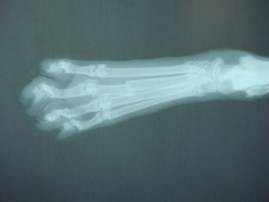

レントゲン検査にて、

右後肢第三中足骨が骨折していることがわかりました。

(右後ろ脚、中指にあたる部分の足の甲)